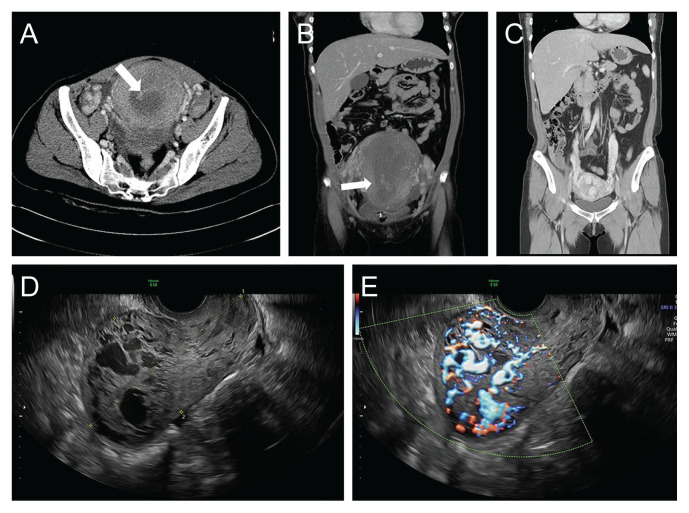

Abstract Image

In an 8-year period at two medical center, 138 patients underwent uterine artery embolization, and 11 of them were diagnosed with uterine necrosis. Among them, three were successfully conceived. However, one of them developed an arteriovenous malformation after an artificial abortion, and another experienced complications, including placenta previa and placenta accreta spectrum, which resulted in early preterm delivery and recurrent postpartum hemorrhage, necessitating subtotal hysterectomy. Therefore, it is crucial to prepare for potential adverse pregnancy outcomes in subsequent pregnancies for patients with a history of uterine necrosis.